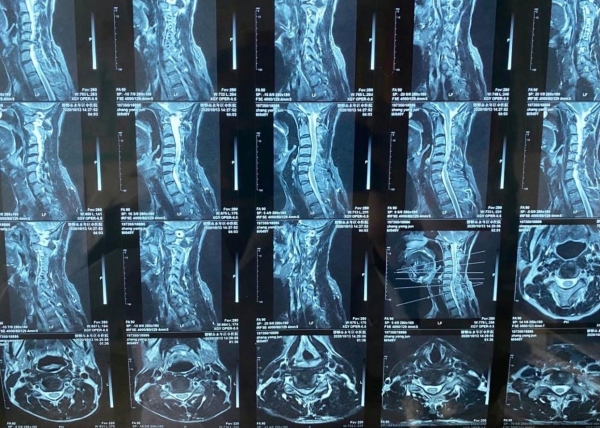

核磁共振技术作为一种先进的影像检查技术,在医疗领域发挥着重要作用。通过该技术,可以清晰观察人体各个器官的结构和变化,从而实现早期病变的筛查和诊断。比如,核磁共振可以对椎体、髓核、纤维环等结构进行清晰观察,并对腰椎间盘突出症状进行定位和诊断,还可以显示脊髓和脊髓肿瘤等。同时,核磁共振对于一些疾病的诊断准确率较高,如脊柱结核和脊柱转移癌的检出率也是比较可观的。

核磁共振检查在诊断某些疾病时发挥着不可替代的作用,适用于许多患者。比如,头部或脊髓等中枢神经系统疾病、乳腺疾病、腹部器官疾病、四肢血管疾病、妇科占位性疾病以及肌肉骨骼系统疾病的患者均可以通过核磁共振检查获取准确的诊断信息。